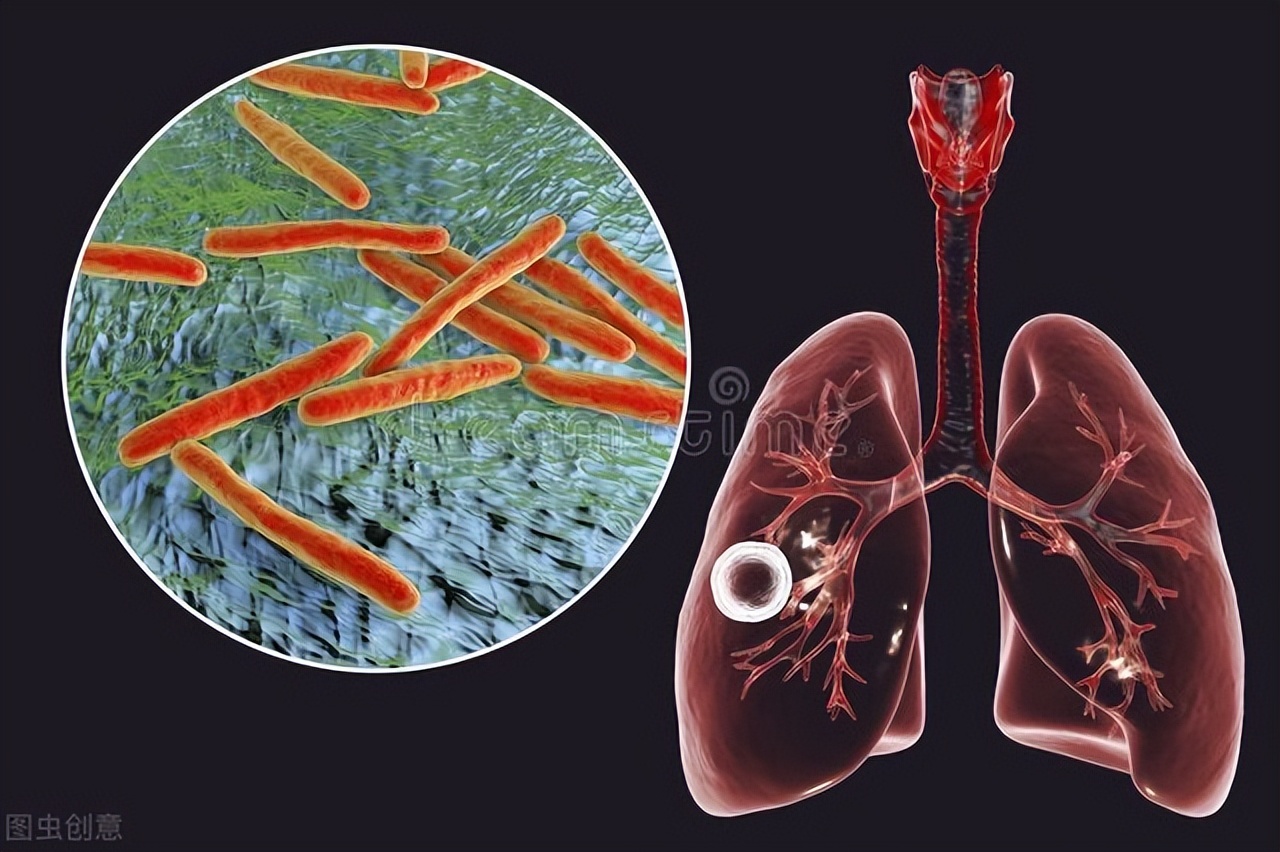

导致肺结核的主要的罪魁祸首就是结核杆菌,那他是如何让我们生病的呢?

结核杆菌可以分为牛结核杆菌和人结核杆菌,但是在我国,牛结核杆菌造成的感染案例少之又少,所以这里我们主要要讲的就是人结核杆菌。顾名思义,结核杆菌的主要传播方式就是人,而传播的途径则是通过呼吸道传播,几乎所有能从呼吸道排出结核杆菌的人都是行走的传染源,这类型又叫做活动性肺结核患者。

结核杆菌的主要传播方式就是空气传播,患者在咳嗽、打喷嚏甚至是说话的时候,体内的结核杆菌都会通过呼吸传播到空气当中。这些进入到空气里的结核杆菌能够存活6个小时以上,作为一种下呼吸道疾病,只要我们吸入了携带结核杆菌的飞沫,当它经过上呼吸道到达肺泡后,就会发生传播。

由于常年与细菌作斗争,我们的普通气道早已经被锻炼的一身铜皮铁骨了,结核杆菌一进入基本上就会被杀死。但是结核杆菌也不是吃素的,既然在这里待不了,那就去别的地方。于是它就一路往下,最后到达肺泡这个世外桃源。

而这里就不得不提一提人体的巨噬细胞了,这是我们体内一种很重要的细胞,是人体免疫系统的先锋军,可是与其他细胞不同的是,他不是很能干,只有当它占据了绝对的优势时,才能够消灭感染,不然的话,可能会成为结核杆菌生存繁衍的温床。

结核菌有很多手段来躲避巨噬细胞,它本身就能够抑制巨噬细胞的生长,使其变成适合自己生存的环境。同时还可以抑制巨噬细胞产生活性氧,活性氧是巨噬细胞杀灭结核杆菌的主要手段,它如此多的手段,能够安安稳稳的生活在我们人体内。